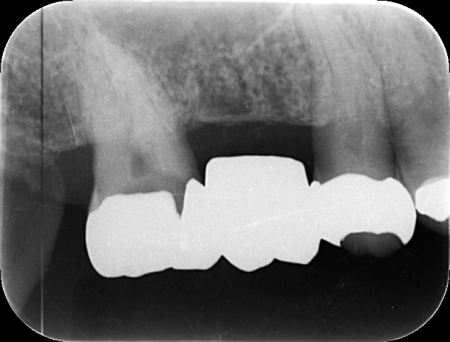

| カウンセリング | 拝見したところ、右上の奥歯には複数の歯をつないだ被せ物であるブリッジが入っていましたが、被せ物の内部で虫歯が再発していました。 レントゲンを撮影して詳しく調べた結果、虫歯は比較的大きく歯の神経に近い深さまで進行していることが確認できました。 このまま放置すると、神経に炎症が起こって強い痛みが出る、神経が死んでしまい歯を温存できなくなるといった可能性があります。 以上のことから、ブリッジを取り外して虫歯を治療する必要があると診断しました。 |

①MTA歯髄温存療法(神経を残す治療) ②根管治療(神経を取る治療) 患者様は「歯を長持ちさせたい」との希望から、①MTA歯髄温存療法を選択されました。 まずブリッジを慎重に取り外し、虫歯を確認します。 数週間後、しみたり痛んだりする症状は認められず、コールドテストとバイタルテストでも歯の神経が問題なく機能している状態であると判断できました。 神経が温存できていることを確認できたため精密な型取りを行い、虫歯の再発リスクが低く強度も高いセラミックのジルコニアでブリッジを新たに作製しました。 |